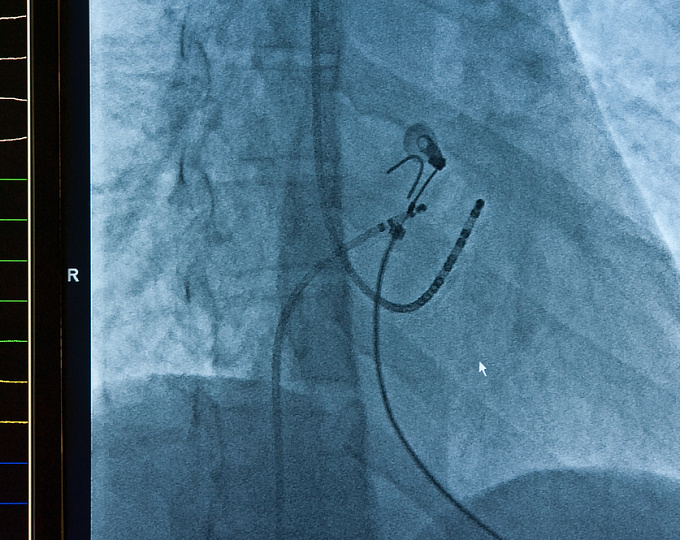

Участниками исследования были пациенты с симптомной пароксизмальной не леченой ФП. Все они рандомизировались в группу выполнения криобалонной аблации или антиаритмической терапии. Также с целью оценки наличия рецидивов ФП после старта терапии всем пациентам имплантировалось устройство мониторинга сердечного ритма.